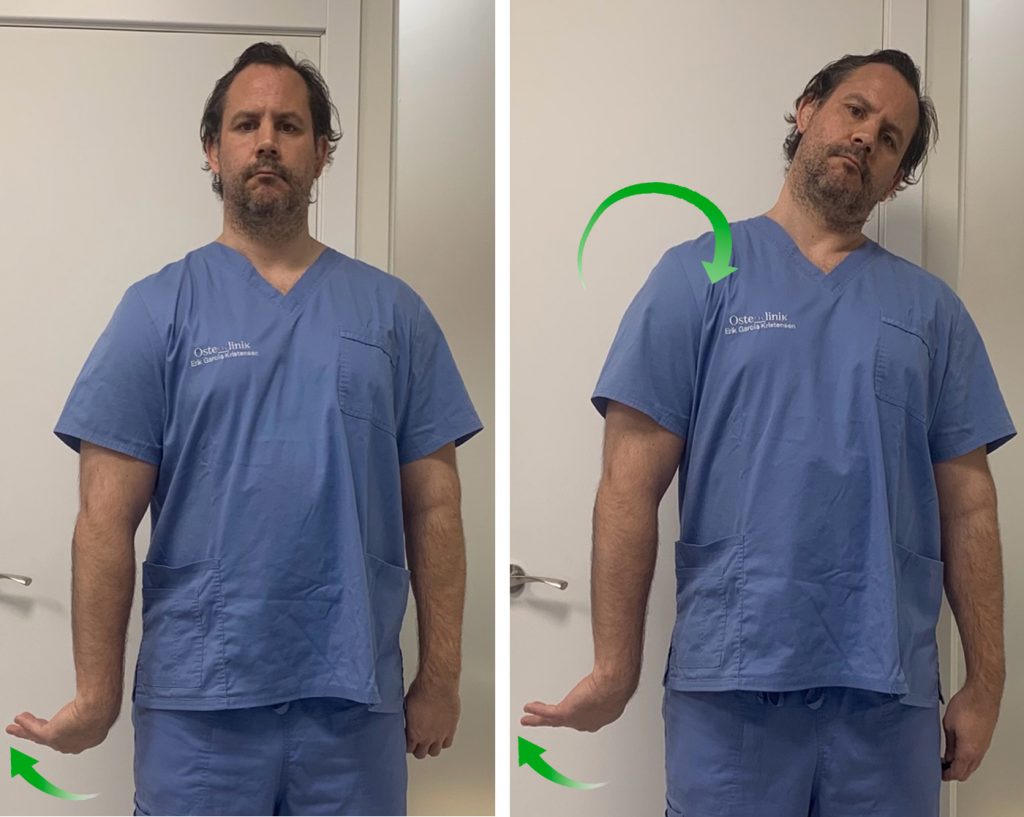

2. Nervio Radial

Vamos a realizar, primero, una puesta en tensión y estiramiento del nervio para después pasar a una movilización.

Partimos de una posición erguida de pie o sentado. Colocamos el brazo estirado y pegado a nuestro cuerpo. Seguidamente realizamos una rotación interna del hombro de forma que la palma de la mano quede mirando hacia lateral y el pulgar hacia atrás.

Nos aseguramos de descender el hombro para generar estiramiento entre las cervicales y el hombro.

Hacemos una flexión palmar de la muñeca e inclinamos lateralmente la cabeza hacia el lado contrario. De esta manera estamos poniendo en tensión el nervio mediano y podemos sentir la sensación de tensión y cierto hormigueo en el brazo y la mano.

Aguantamos unos segundos en esta posición y pasamos a trabajar el deslizamiento del nervio. Para ello, inclinamos la cabeza hacia el lado afecto (deberemos notar en este momento que desaparece la tensión y el hormigueo).

Y ahora volvemos a inclinar la cabeza hacia el lado contrario a la vez que hacemos una flexión dorsal de la muñeca. Cuando llegamos al límite de movimiento, inclinamos la cabeza de nuevo hacia el lado afecto y hacemos otra vez flexión palmar de la muñeca.

El ejercicio consiste en alternar inclinación contraria de la cabeza + flexión dorsal de la muñeca e inclinación hacia el lado de la lesión + flexión palmar.

Reposo

Estiramiento

Movilización- deslizamiento